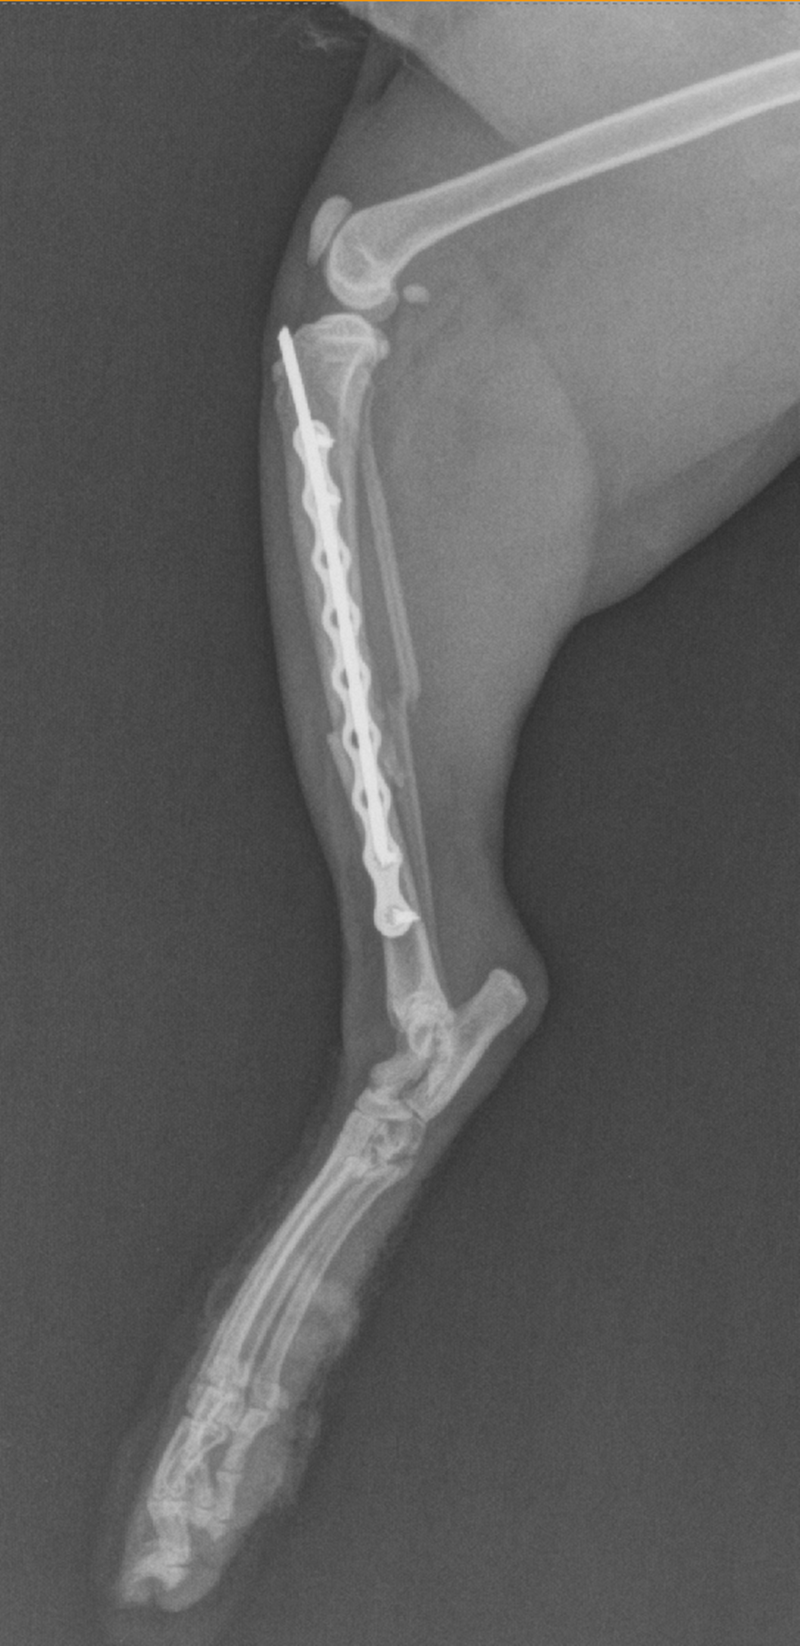

Ortopedija ili ortopedska kirurgija je grana kirurgije koja se bavi bolestima i liječenjem mišićno-koštanog sustava. Zbog kompleksnosti ozljeda pristup pacijentu je temeljit i sistematičan, a između ostalog uključuje opći pregled, promatranje kretanja, provjere opsega pokretljivosti i bolnosti, naposljetku se pristupa dodatnim dijagnostičkim pretragama kao što je rendgenološka pretraga. Najčešće ozljede uključuju prijelome kostiju i luksacije zglobova. Lom je svaki prekid kontinuiteta kosti, a luksacije su potpuna odvajanja krajeva kostiju koji se normalno spajaju u zglob. Glavni uzroci su prometne nezgode i padovi. Naša ambulanta koristi najmodernije implantate i tehnike sanacije dostupne u veterinarskoj medicini.